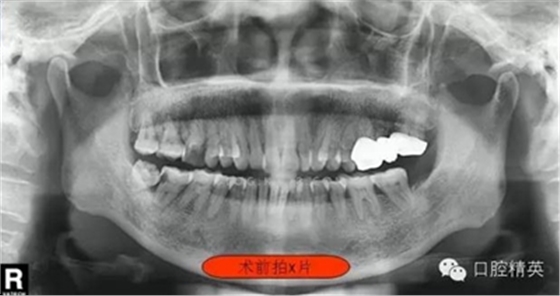

圖一

這位患者女性,年齡60歲。遠中鄰面深齲,探診疼痛不適。主訴有夜間疼痛加重,叩診(+),一度松動,遠中根部牙槽骨吸收,診斷牙髓炎。后來右下8拔除。